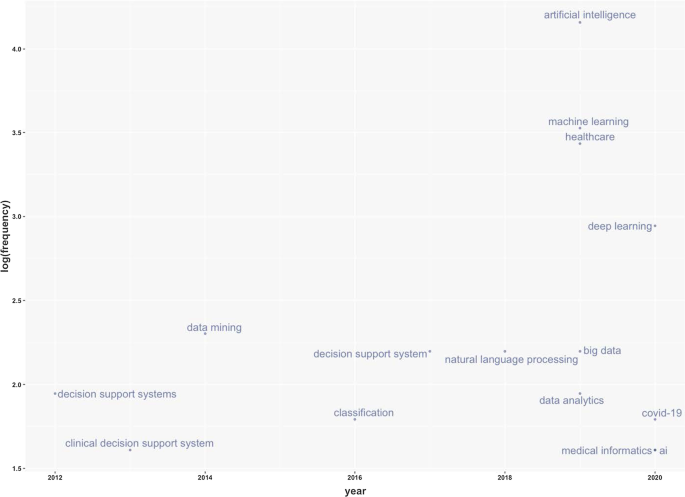

Patients can stay informed and engaged in their care by communicating with their medical teams during hospital stays.

Additionally, AI can contribute to optimising logistics processes, for instance, realising drugs and equipment in a just-in-time supply system based totally on predictive algorithms [ 73 , 74 ]. Interesting applications can also support the training of personnel working in health services. This evidence could be helpful in bridging the gap between urban and rural health services [ 75 ]. Finally, health services management could benefit from AI to leverage the multiplicity of data in electronic health records by predicting data heterogeneity across hospitals and outpatient clinics, checking for outliers, performing clinical tests on the data, unifying patient representation, improving future models that can predict diagnostic tests and analyses, and creating transparency with benchmark data for analysing services delivered [ 51 , 76 ].

Predictive medicine

Another relevant topic is AI applications for disease prediction and diagnosis treatment, outcome prediction and prognosis evaluation [ 72 , 77 ]. Because AI can identify meaningful relationships in raw data, it can support diagnostic, treatment and prediction outcomes in many medical situations [ 64 ]. It allows medical professionals to embrace the proactive management of disease onset. Additionally, predictions are possible for identifying risk factors and drivers for each patient to help target healthcare interventions for better outcomes [ 3 ]. AI techniques can also help design and develop new drugs, monitor patients and personalise patient treatment plans [ 78 ]. Doctors benefit from having more time and concise data to make better patient decisions. Automatic learning through AI could disrupt medicine, allowing prediction models to be created for drugs and exams that monitor patients over their whole lives [ 79 ].